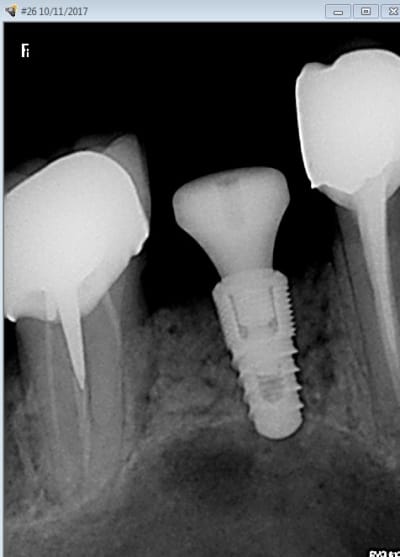

Premiere utilisation des forets ce matin.

Mise en place d'un naturall + ETK 4 x 8.

Dispo : 6 mm : arret du forage a 5 , puis foret "versah" , on sent bien quand on passe la corticale du sinus.

Verification quand meme de l'étanchéité, un peu bout de PRF au fond et c'est bon.